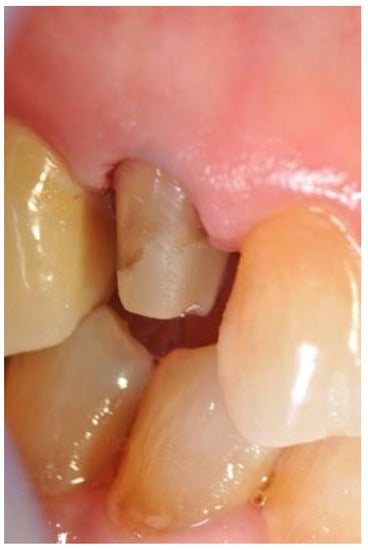

Abutment tooth preparations of Group A were performed following the generally accepted recommendations for CAD/CAM (Computer-Aided Design/Computer-Aided Manufacturing)-restorations with supragingivally located margins in order to remain visible [20]. In Group B, the margins were placed 0.5–1.0 mm into the sulcus and in Group C, the margins were placed around 1.5–2.0 mm in depth. Clinical pictures were taken of each quadrant and the corresponding preparations (Figure 2).

Figure 2. The abutment after preparation.